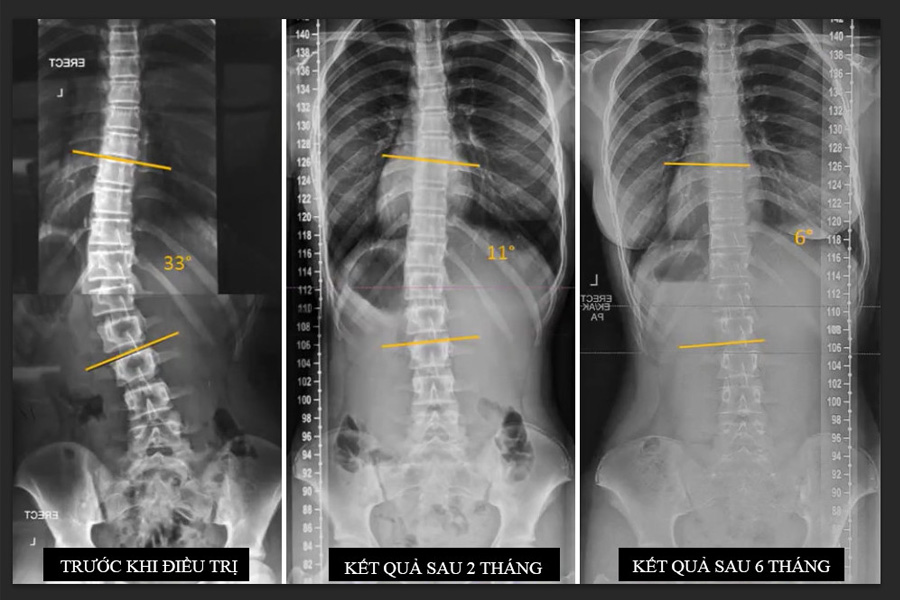

Cong vẹo cột sống là bệnh dị tật ở cột sống có biểu hiện cột sống bị cong bất thường sang trái, bên phải so với trực của cơ thể hoặc bị vẹo xoay phức tạp. Căn bệnh này thường gặp ở cả trẻ em và người lớn.

Điều trị cong vẹo cột sống tại phòng khám SCC